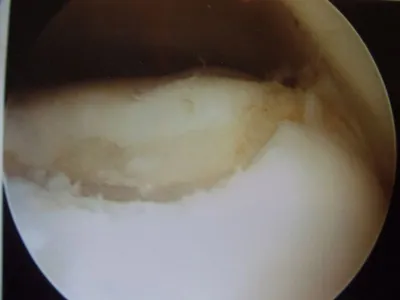

A series of intraop ankle arthroscopy pics of synovial chondromatosis with OCD talus and tibia and microfracture.

Pic of one of the nodules inside the ankle joint.